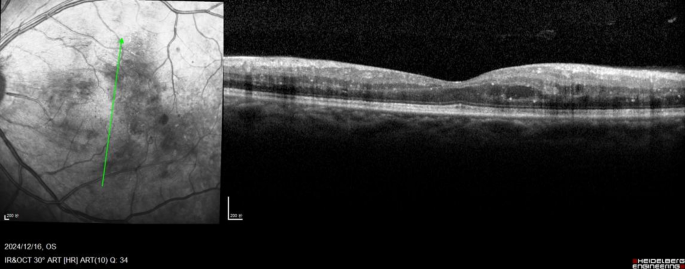

OCT images were acquired using 6-mm vertical and horizontal scans centered on the fovea in high-resolution mode with spectral domain OCT (SD-OCT, Heidelberg Spectralis OCT, Heidelberg Engineering, Germany). Recorded quantitative variables included (1) central macular thickness (CMT) and (2) the total number of hyperreflective foci (HRF) across retinal layers. Qualitative parameters were assessed for (1) size of intraretinal cysts (IRC), (2) integrity of the ELM and EZ, (3) presence of disorganization of the inner retinal layers (DRIL), and (4) presence of subfoveal fluid (SRF). All the subjects underwent examinations twice. All OCT images were analysed by the blinded retina specialist(Li-na Lv) and averages were determined. According to the TCED-HFV grading system (Table 1), the DME was divided into early, advanced, severe, and atrophic stages10 (Table 2, represented in Figs. 1, 2, 3 and 4).

Atrophic DME Central retinal thinning with DRIL. The ELM and the EZ are still gradable subfoveally, and there are several hyperreflective foci in the outer nuclear layer and OPL. Thickness and volume are below normal values, but some moderate intraretinal cysts are present. The TCED-HFV grading is T = 0, C = 1, E = 0, D = 1, H = 0, F = 0, and V = 0.